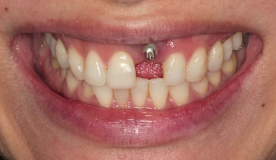

UNCUT! Immediate Tooth Replacement with BLX Implant, Socket Xenograft

CAT# ULS-002

UNCUT! Live Surgery - Immediate Tooth Replacement with BLX Implant, Socket Xenograft, ‘Neck Pillow’ Soft Tissue Graft & Digital Workflow

Dr Sascha A Jovanovic

In this comprehensive new surgical video, Dr. Sascha A. Jovanovic, Periodontist Master Clinician from Los Angeles, CA pre... -